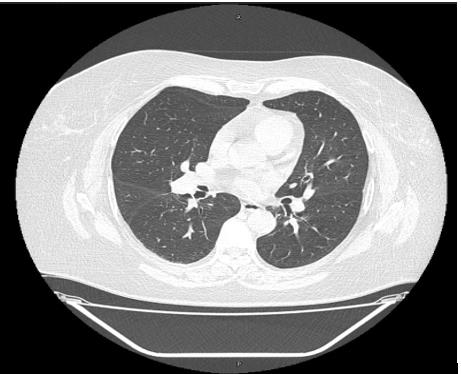

The erythrocyte sedimentation rate was reported as 0.0 mm/ hour. The blood chemistry panel reported Alanine Aminotransferase 35.0U/L, Aspartate Aminotransferase 18.0 U/L, Alkaline Phosphatase 79.0 U/L, Lactate Dehydrogenase 147.0 U/L, Gamma glutamyltransferase 42.0 U/L, albumin 4.4 g/dl, albumin/Globulin index 1.5, Creatine Kinase 22.0 U/L, C-Reactive Protein 4.56 mg/L (normal range for the laboratory <5mg/L), D- dimer <0.15 mg/L (normal range for the laboratory 0-0,7mg/L), Ferritin 204.39 ng/ ml (normal range for the laboratory 11.1-264 ng/ml). The chest X-ray revealed reduced radiodensity in pulmonary parenchyma with diffuse and fine interstitial thickening at lower lung lobes (Figure 1), (although the chest computed tomography (CT) did not showed them), the most important finding was pulmonary arterial hypertension.

Figure 1: Chest X-ray.

The chest X-ray revealed reduced radiodensity in pulmonary parenchyma with diffuse and fine interstitial thickening at lower lung lobes, the most

important finding was pulmonary arterial hypertension.

This case shows two different but very relevant issues. First of all, the possibility of developing COVID-19 despite an active vaccine and secondly, its efficiency to prevent severe outcomes in a fragile woman with severe COPD. She received two doses of the sputnik vaccine on time, although the symptoms onset appeared 10 days after receiving the last dose, the immunity achieved was enough to avoid hospital admission. Data of the phase III interim report of Sputnik V showed that about one quarter of those who entered the trail had comorbidities, a known risk for COVID-19 severity. A time-resolved plot of the incidence rate showed that the immunity required to prevent disease arose within 18 days of the first dose. In all age groups, the anecdotal case histories of those vaccinated but infected suggest that the severity of disease decreases as immunity develops [11]. The vaccine that was applied to the patient is characterized for having recombinant adenovirus as vaccine vectors and being able to provide immunity after just a single dose [10]. Nevertheless, she received two doses, the period time between the last one and the symptoms onset were not enough to avoid the infection. However, the first dose she received was sufficient to achieve immunity to prevent a severe infection demonstrated by her clinical picture, chest x-ray, chest CT, SaO2 and lack of increased inflammatory markers (CRP, ferritin, VSG).